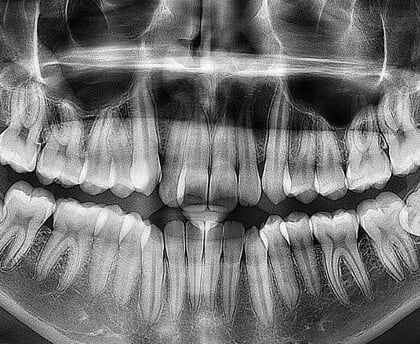

Panoramă dentară

Radiografiile panoramice oferă o imagine completă a întregii cavități bucale, inclusiv a dinților, maxilarelor și articulațiilor temporomandibulare

Radiografiile panoramice dentare sunt o altă metodă importantă de imagistică medicală utilizată în stomatologie. Aceste radiografii oferă o imagine completă a întregii cavități bucale, inclusiv a dinților, oaselor maxilarelor și articulațiilor temporomandibulare. În acest articol, ne vom concentra asupra radiografiilor panoramice dentare, vom explora tehnologia din spatele acestora și vom evidenția beneficiile și aplicațiile lor în domeniul stomatologiei.

Radiografiile panoramice dentare, cunoscute și sub numele de radiografii panoramică sau "panoramă", sunt o tehnică importantă de imagistică medicală utilizată în stomatologie. Aceste radiografii sunt diferite de radiografiile intraorale, care se concentrează pe un singur dinte sau pe o regiune specifică a gurii. În schimb, radiografiile panoramice oferă o vedere completă a cavității bucale într-o singură imagine.

Vedere completă: Radiografiile panoramice oferă o vedere completă a cavității bucale, inclusiv a tuturor dinților, oaselor maxilarelor, sinusurilor paranazale, articulațiilor temporomandibulare și a altor structuri.